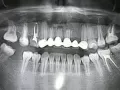

Три года назад мне установили металлокерамический резец. Я перестала кусать пищу передними зубами, боясь, что он не выдержит нагрузки, в общем, берегла как могла. Несколько дней назад заметила, что десна над ним вспухла, но она не красная, а беловатая. Над зубом дугой красная полоса, которая кровоточит при задевании её щеткой.

Обычно у меня возникали припухлости на деснах, снимала их довольно-таки быстро обычной содой, а тут полоскать начала Стоматофит, думала, если не сниму опухоль, то приостановлю инфекцию. Ничего не болит даже при нажатии, однако есть неприятные ощущения. Чувствую этот зуб.

С чем связано это воспаление? Неужели из-за этой опухоли мне будут вынимать искусственный зуб?

Естественно, коронку необходимо извлечь, далее зуб перелечить (если это ещё возможно). По симптомам — у Вас хроническое воспаление, причина которому — некачественное лечение каналов зуба.